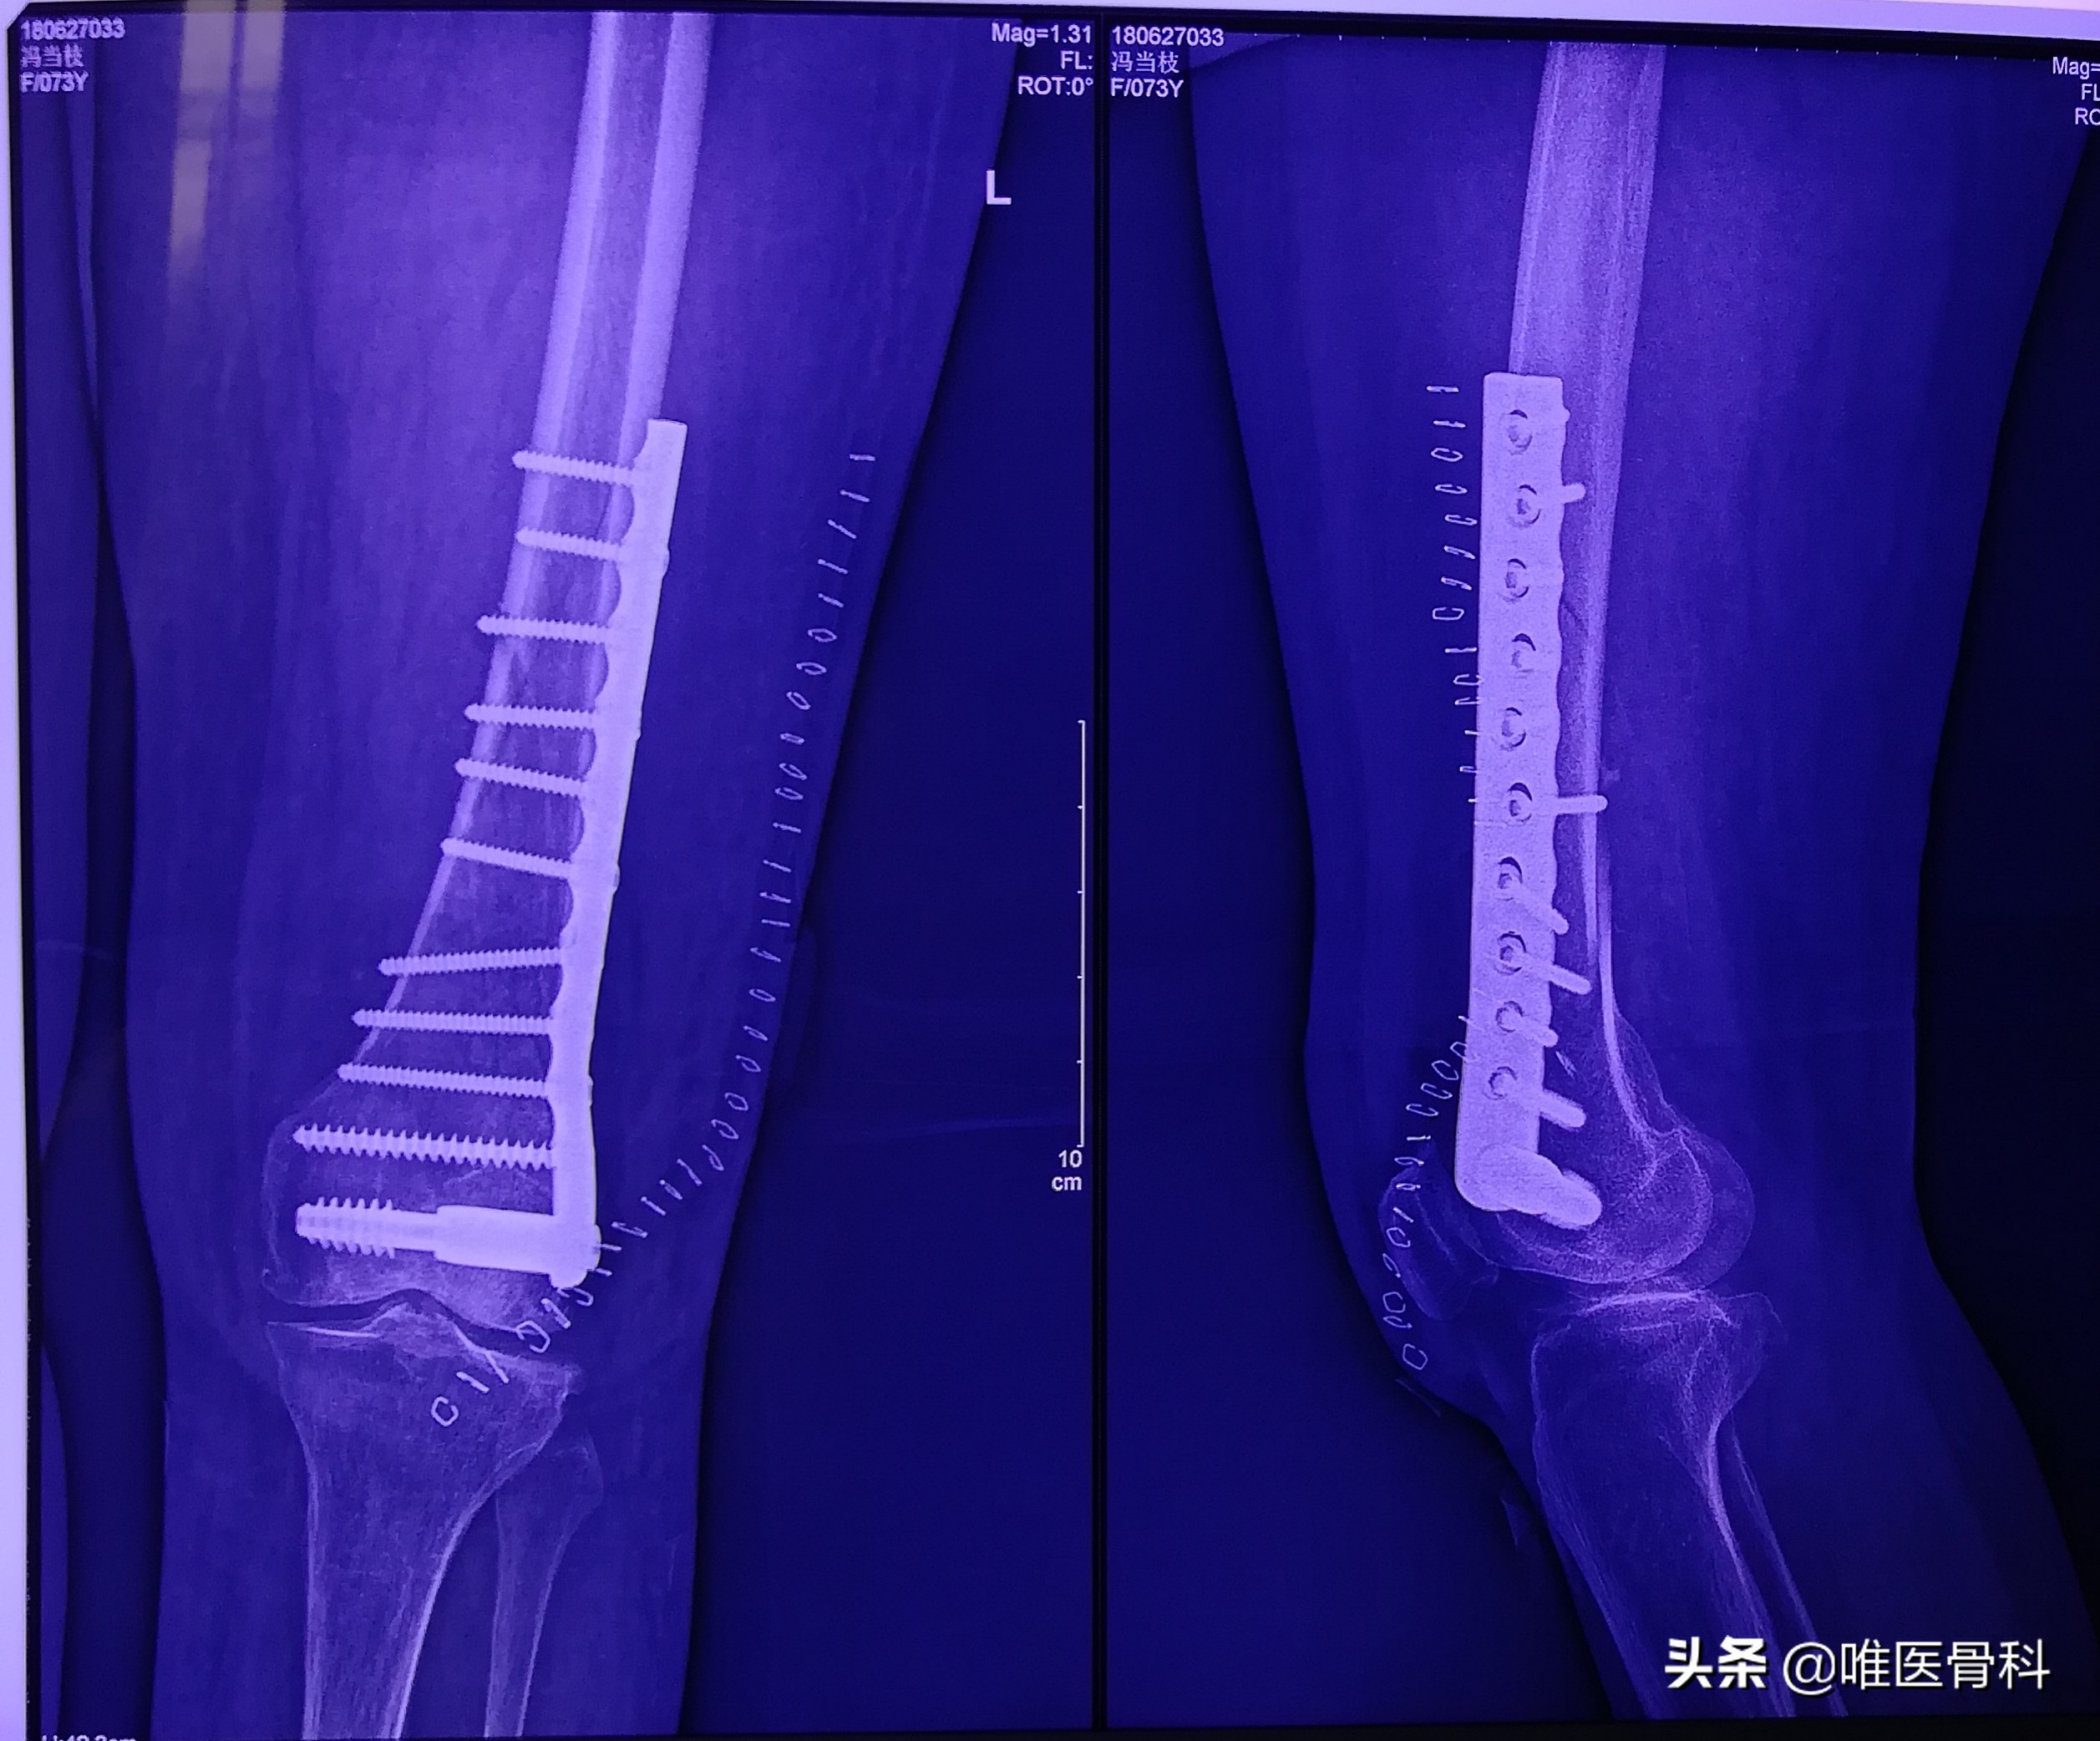

1.X线检查

凡疑为骨折者应常规进行X线拍片检查,可显示临床上难以发现的不完全性骨折、深部骨折、关节内骨折和小的撕脱性骨折等,即使临床上已表现为明显骨折者,X线拍片检查也是必需的,可以了解骨折的类型和具体情况,对治疗具有指导意义。

X线摄片应包括正、侧位片,必须包括邻近关节,有时需加摄斜位、切线位,行健侧相应部位的X线片可做对比。

2.固定及原理

骨折复位后,因不稳定,容易发生再移位,加重周围软组织损伤和剧烈疼痛。开放骨折还会引起感染,因此要采用不同的方法将其固定在满意的位置,使其逐渐愈合。

常用的固定方法有:小夹板、石膏绷带、外固定支架、牵引制动固定等,这些固定方法称外固定。

如果通过手术切开用螺钉、钢针、钢丝、钢板、髓内针、及其组合等固定,则称内固定。

螺钉、钢针、钢丝单独或通过钢板、髓内钉将骨折缝合起来,起到保持复位的固定作用,经过一定时间,骨折愈合,恢复功能。